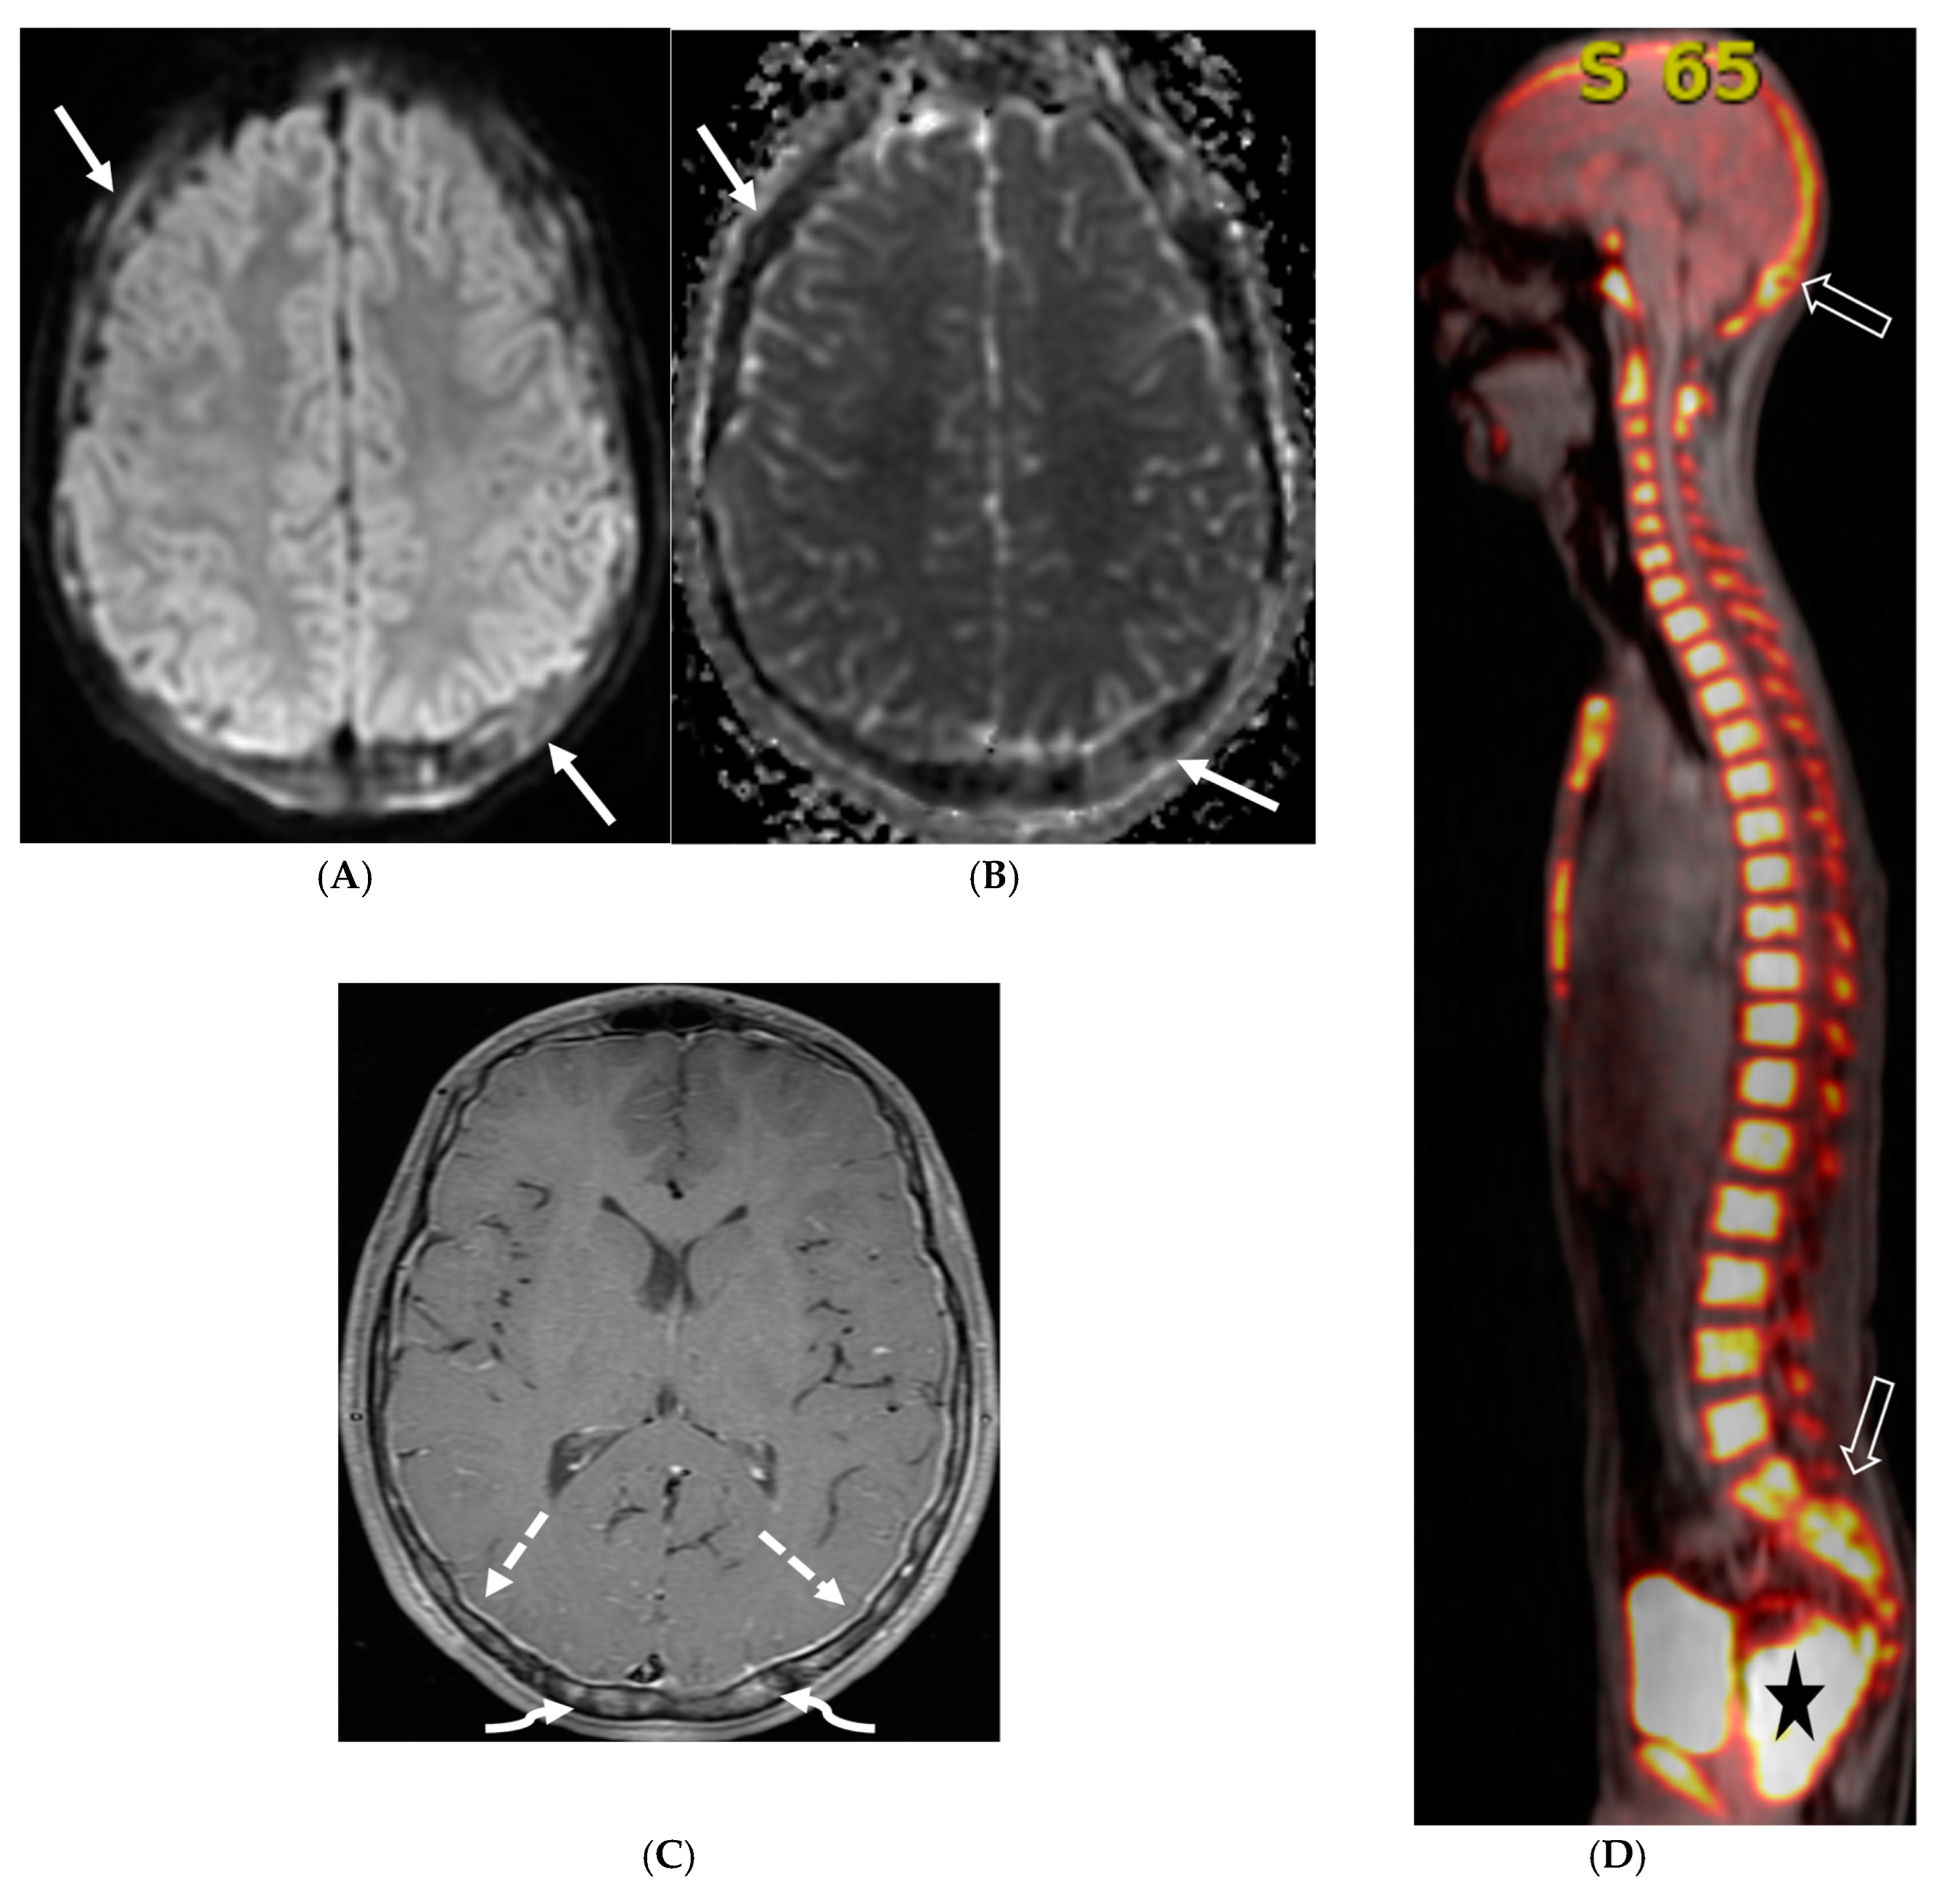

Figure 3.

18-year-old presented with headache, persistent vomiting and weight loss. History of sarcoidosis diagnosed 2 years ago. Axial Fluid Attenuated Inversion Recovery (FLAIR) (A), Axial T1 post contrast (B), Axial T1 inversion recovery post contrast (C) and Coronal Positron Emission Tomograpy (PET) scan (D): There is a heterogeneously enhancing ill-defined area of T2/FLAIR hyperintensity involving the medial aspect of the left globus pallidus (arrows), anterior aspect of the left thalamus and left hypothalamic region. Diffuse enhancement of the basal meninges, tentorium, throughout perisylvian sulci (arrow heads), along the infundibulum, and posteriorly at the craniocervical junction. There is also enhancement along optic nerve sheath (dashed arrows). Features are highly consistent with extensive neurosarcoidosis given the previous history of thoracic sarcoid. PET scan from 2 years earlier demonstrating avid uptake of radiotracer (curved arrows). Radiologically, the differential diagnosis includes tuberculosis and metastatic process. Patient made complete recovery after treatment for sarcoid.